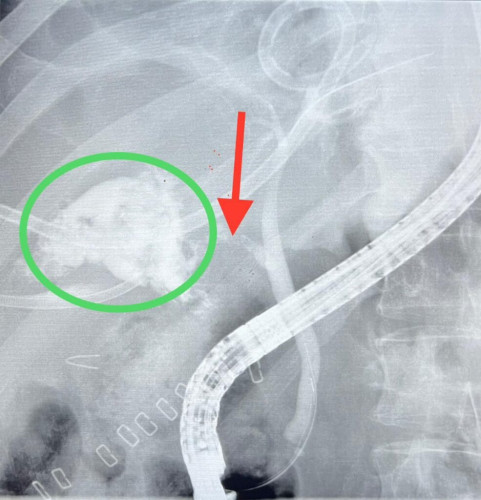

وأوضحت “الصحة” ان الفريق الطبي قد أجرى منظار مجهري للقنوات الصفراوية تحت تخدير عام وبإستخدام الأشعة، وتم فتح صمّام القناة الصفراوية، وزرع دعامة بلاستيكية لسد منطقة التسريب بنجاح دون حدوث أي مضاعفات.